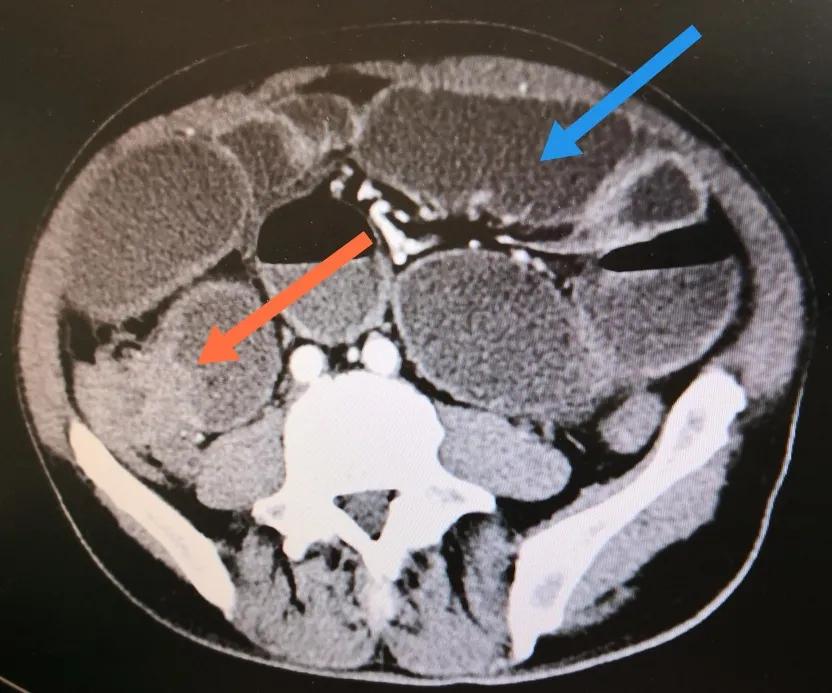

粉红色箭头所示为回盲部肿瘤,已侵犯回肠未端导致全小肠梗阻

蓝色箭头为小肠梗阻后所形成的气液平面,红色箭头所指为空虑的结肠